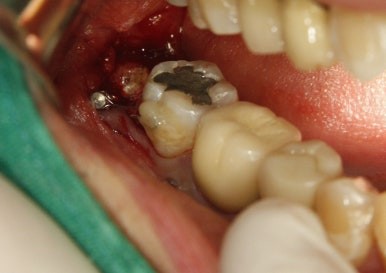

수술날짜를 잡고 나머지 뿌리도 깨끗하게 발치완료~

이 환자의 경우 다른 환자와 다른 것

이 사랑니가 누워있지 않고 서있어서 오히려 교정력을 주기가 더 어려웠다.